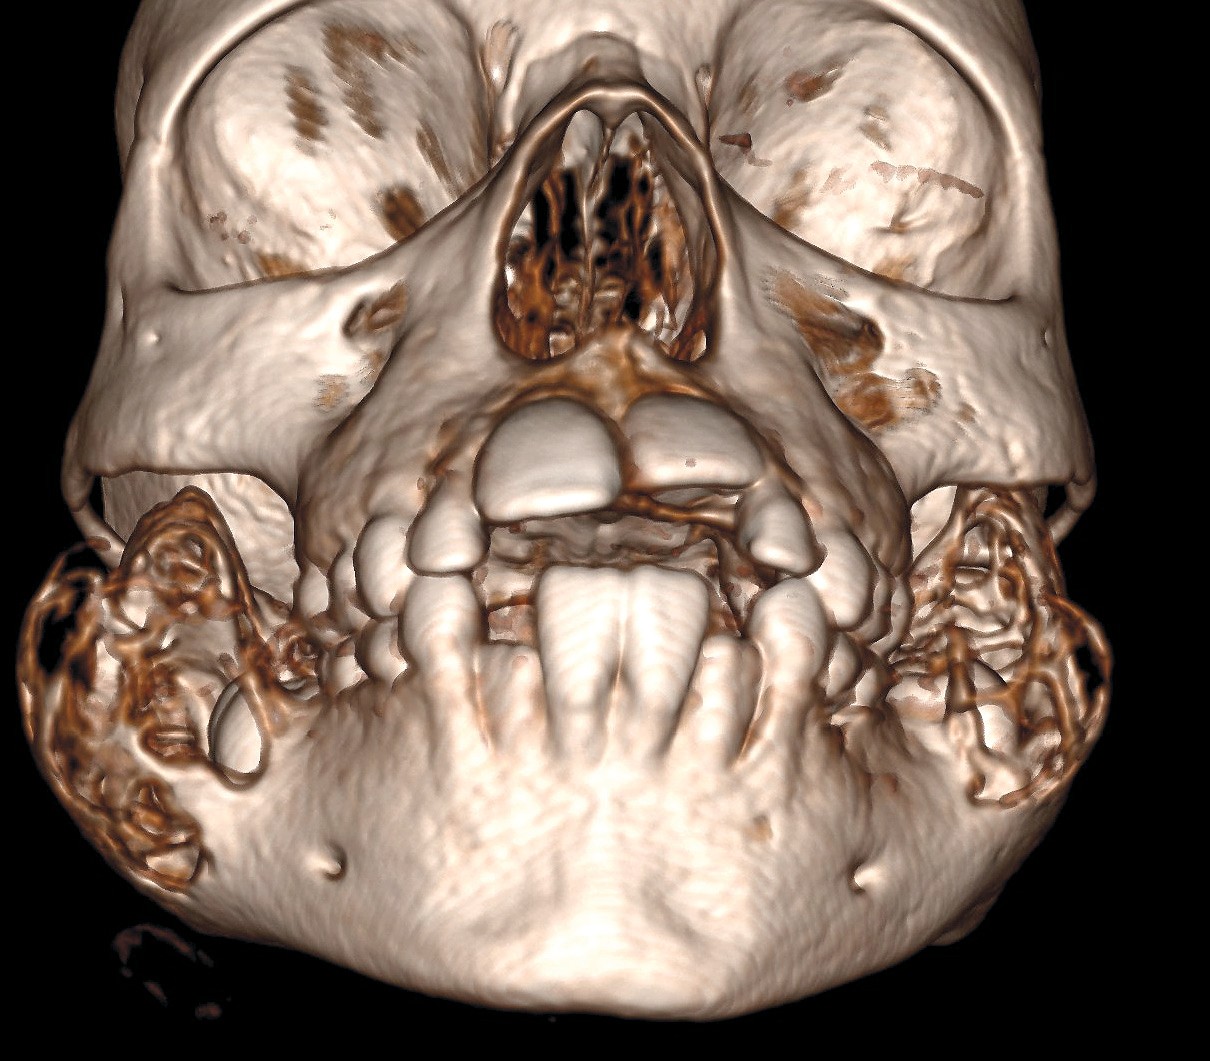

3D-CT-bildet viser ansiktsskjelettet til en tidligere frisk seksåring som ble henvist til utredning ved barneavdelingens poliklinikk på grunn av hypertrofiske kinn bilateralt. Kinnene hadde ifølge familien vært slik siden fødsel. CT av ansiktsskjelettet rekvirert på spørsmål om hypertrofi av musculus masseter avslørte symmetriske multilokulære dysplastiske ekspansjoner i ramus mandibulae på begge sider. Man fikk derfor mistanke om diagnosen kjerubisme. Fibrøs dysplasi (FD) var en aktuell differensialdiagnose, men man forventer ofte mer sklerotiske forandringer ved denne tilstanden.

Genetisk testing viste at pasienten var heterozygot for en genfeil på SH3BP2-genet som er forbundet med autosomalt dominant kjerubisme (1–3). Genet koder for et protein som fører til en kombinasjon av inflammasjon og økt produksjon av osteoklaster i kjevebeinet, som leder til den karakteristiske cystiske ekspansjonen (3, 4).